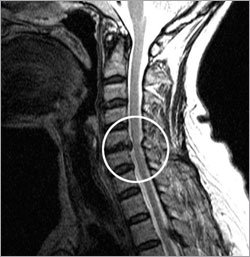

목디스크란 목뼈 사이에 있는 디스크가 손상되어 신경을 압박하는 질환을 의미합니다. 디스크는 젤리와 같은 수핵과 섬유륜으로 구성되어 있습니다. 섬유륜이 손상되면 수핵이 밖으로 밀려나와 신경을 압박하게 됩니다.

경추 디스크가 압박되거나 탈출하면 주변 신경을 자극하여 방사성 팔 통증이 발생할 수 있습니다. 이 통증은 일반적으로 목에서 어깨, 팔, 손이나 손가락으로 내려가는 특정 경로를 따릅니다. 영향을 받은 팔의 무감각, 저림 또는 약화가 동반될 수 있습니다.

더 심한 경우에는 목 디스크 문제가 신경계에 영향을 미쳐 균형 감각과 협응력(신체의 신경 기관, 운동 기관, 근육 따위가 서로 호응하며 조화롭게 움직일 수 있는 능력) 장애를 유발할 수 있습니다. 걸을 때 불안정하거나 균형을 유지하기 어렵고 움직임이 서툴게 느껴질 수 있습니다. 이러한 증상이 나타난다면 추가 합병증을 예방하기 위해서라도 즉시 병원에 내원하여 진료를 받는 것이 좋습니다.